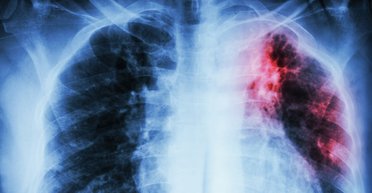

Принято считать, что туберкулез — это болезнь маргинальных групп населения, однако почти 80% всех заболевших — социально благополучные люди. Как выстоять в схватке с микобактерией и общественной стигматизацией, рассказывает Фокус